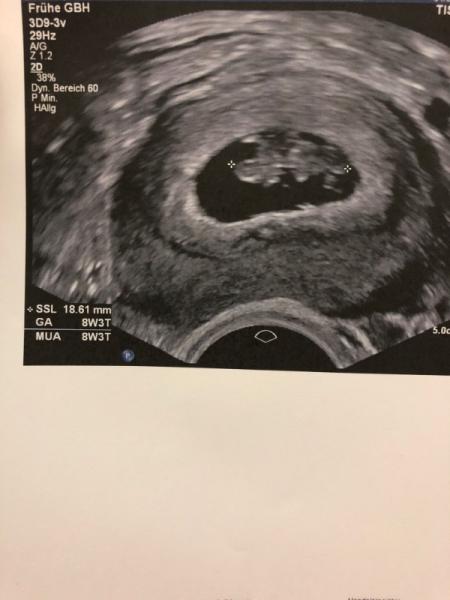

Ich melde mich mal wieder aus dem Krankenhaus. Hatte ja schon geschrieben, dass ich die heftige Form der Übelkeit und Erbrechen habe gestern hat’s mich wieder gerissen, sodass ich wieder im Krankenbett mit Infusionen liege. Das einzigst positive daran ist das neue Bild von unseren Baby. Es ist schon wirklich groß geworden, Herzchen schlägt schön und morgen bin ich dann schon in der 10. Woche :)

Bild zu Krankenhaus Part 2 - Forum für Januar - Mamis